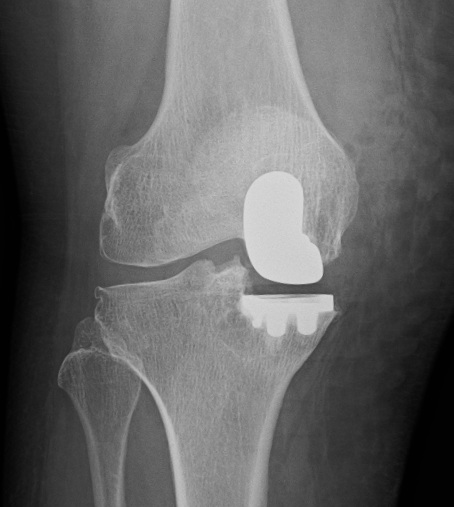

Example of Partial Knee Replacement

A front on view of a partial knee replacement, in this case repalcing the medial, or inside, of the knee